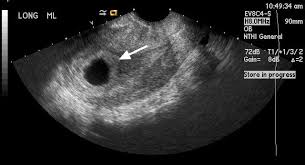

Is it normal to have fluid in the cul-de-sac in early pregnancy?

It’s important to understand that fluid in the cul-de-sac during early pregnancy doesn’t automatically mean an ectopic pregnancy. While it can be a sign, other factors need to be considered. For example, hCG levels that aren’t rising as expected and an ultrasound that can’t pinpoint the pregnancy location might point towards an ectopic pregnancy. In such cases, procedures like dilation and curettage (D&C) or manual vacuum aspiration (MVA) might be recommended. These procedures can help determine if a gestational sac or chorionic villi are present, which can offer more definitive information.

However, cul-de-sac fluid can also occur due to other reasons, such as a normal pregnancy or fluid buildup from a prior surgery. Therefore, it’s crucial to consult with a healthcare professional who can assess your specific situation. They will consider all factors, including your medical history, symptoms, and test results, to arrive at an accurate diagnosis and guide your care.

While fluid in the cul-de-sac can sometimes be a sign of an ectopic pregnancy, it’s not always the case. The cul-de-sac is a small pouch located behind the uterus. It’s normal to have a small amount of fluid in the cul-de-sac, especially after your period. During early pregnancy, this fluid can sometimes increase due to hormonal changes, blood flow, and the growing uterus.

However, if the amount of cul-de-sac fluid is significant, or if it’s accompanied by other symptoms like pain, bleeding, or fever, it’s important to consult a doctor. These symptoms could indicate a more serious condition, such as an ectopic pregnancy.

It’s crucial to remember that an ectopic pregnancy occurs when a fertilized egg implants outside the uterus, typically in the fallopian tube. This is a serious medical condition that requires immediate attention. If you’re experiencing any of these symptoms, seek medical care immediately.

A doctor will perform a thorough evaluation, which may include a pelvic exam, ultrasound, and blood tests. Based on the results, they will determine the cause of the cul-de-sac fluid and recommend the appropriate treatment plan. Remember, early detection and prompt treatment are crucial for achieving the best outcome.